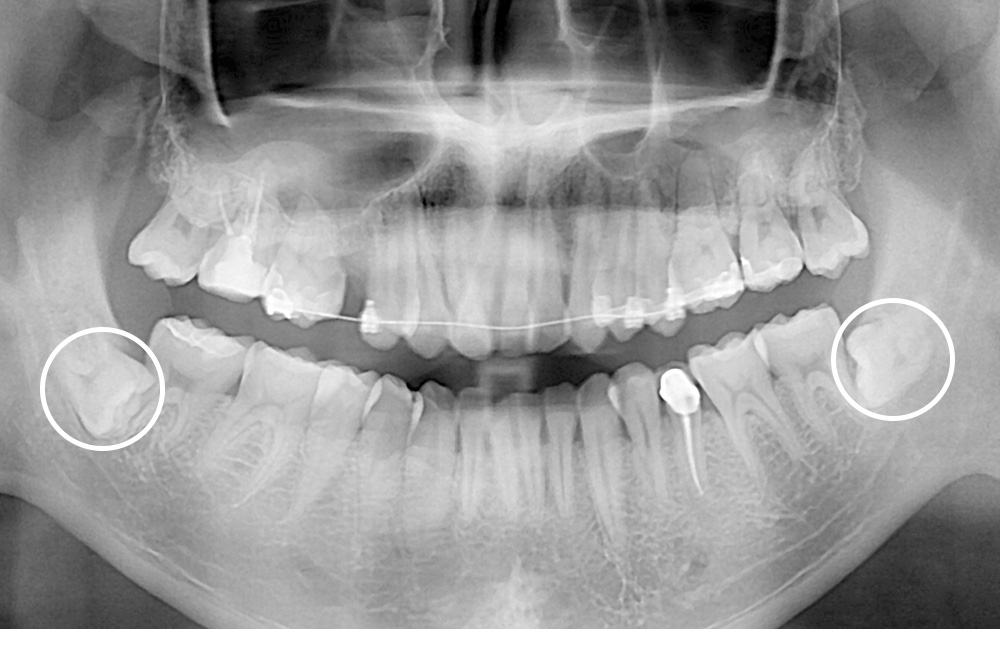

[사랑니] 매복 사랑니 발치

치료전 : 2017-10-18

치료후 : 2017-11-02

세종치과는 구강악안면외과학 박사이신 원장님이 발치하는 치과입니다.